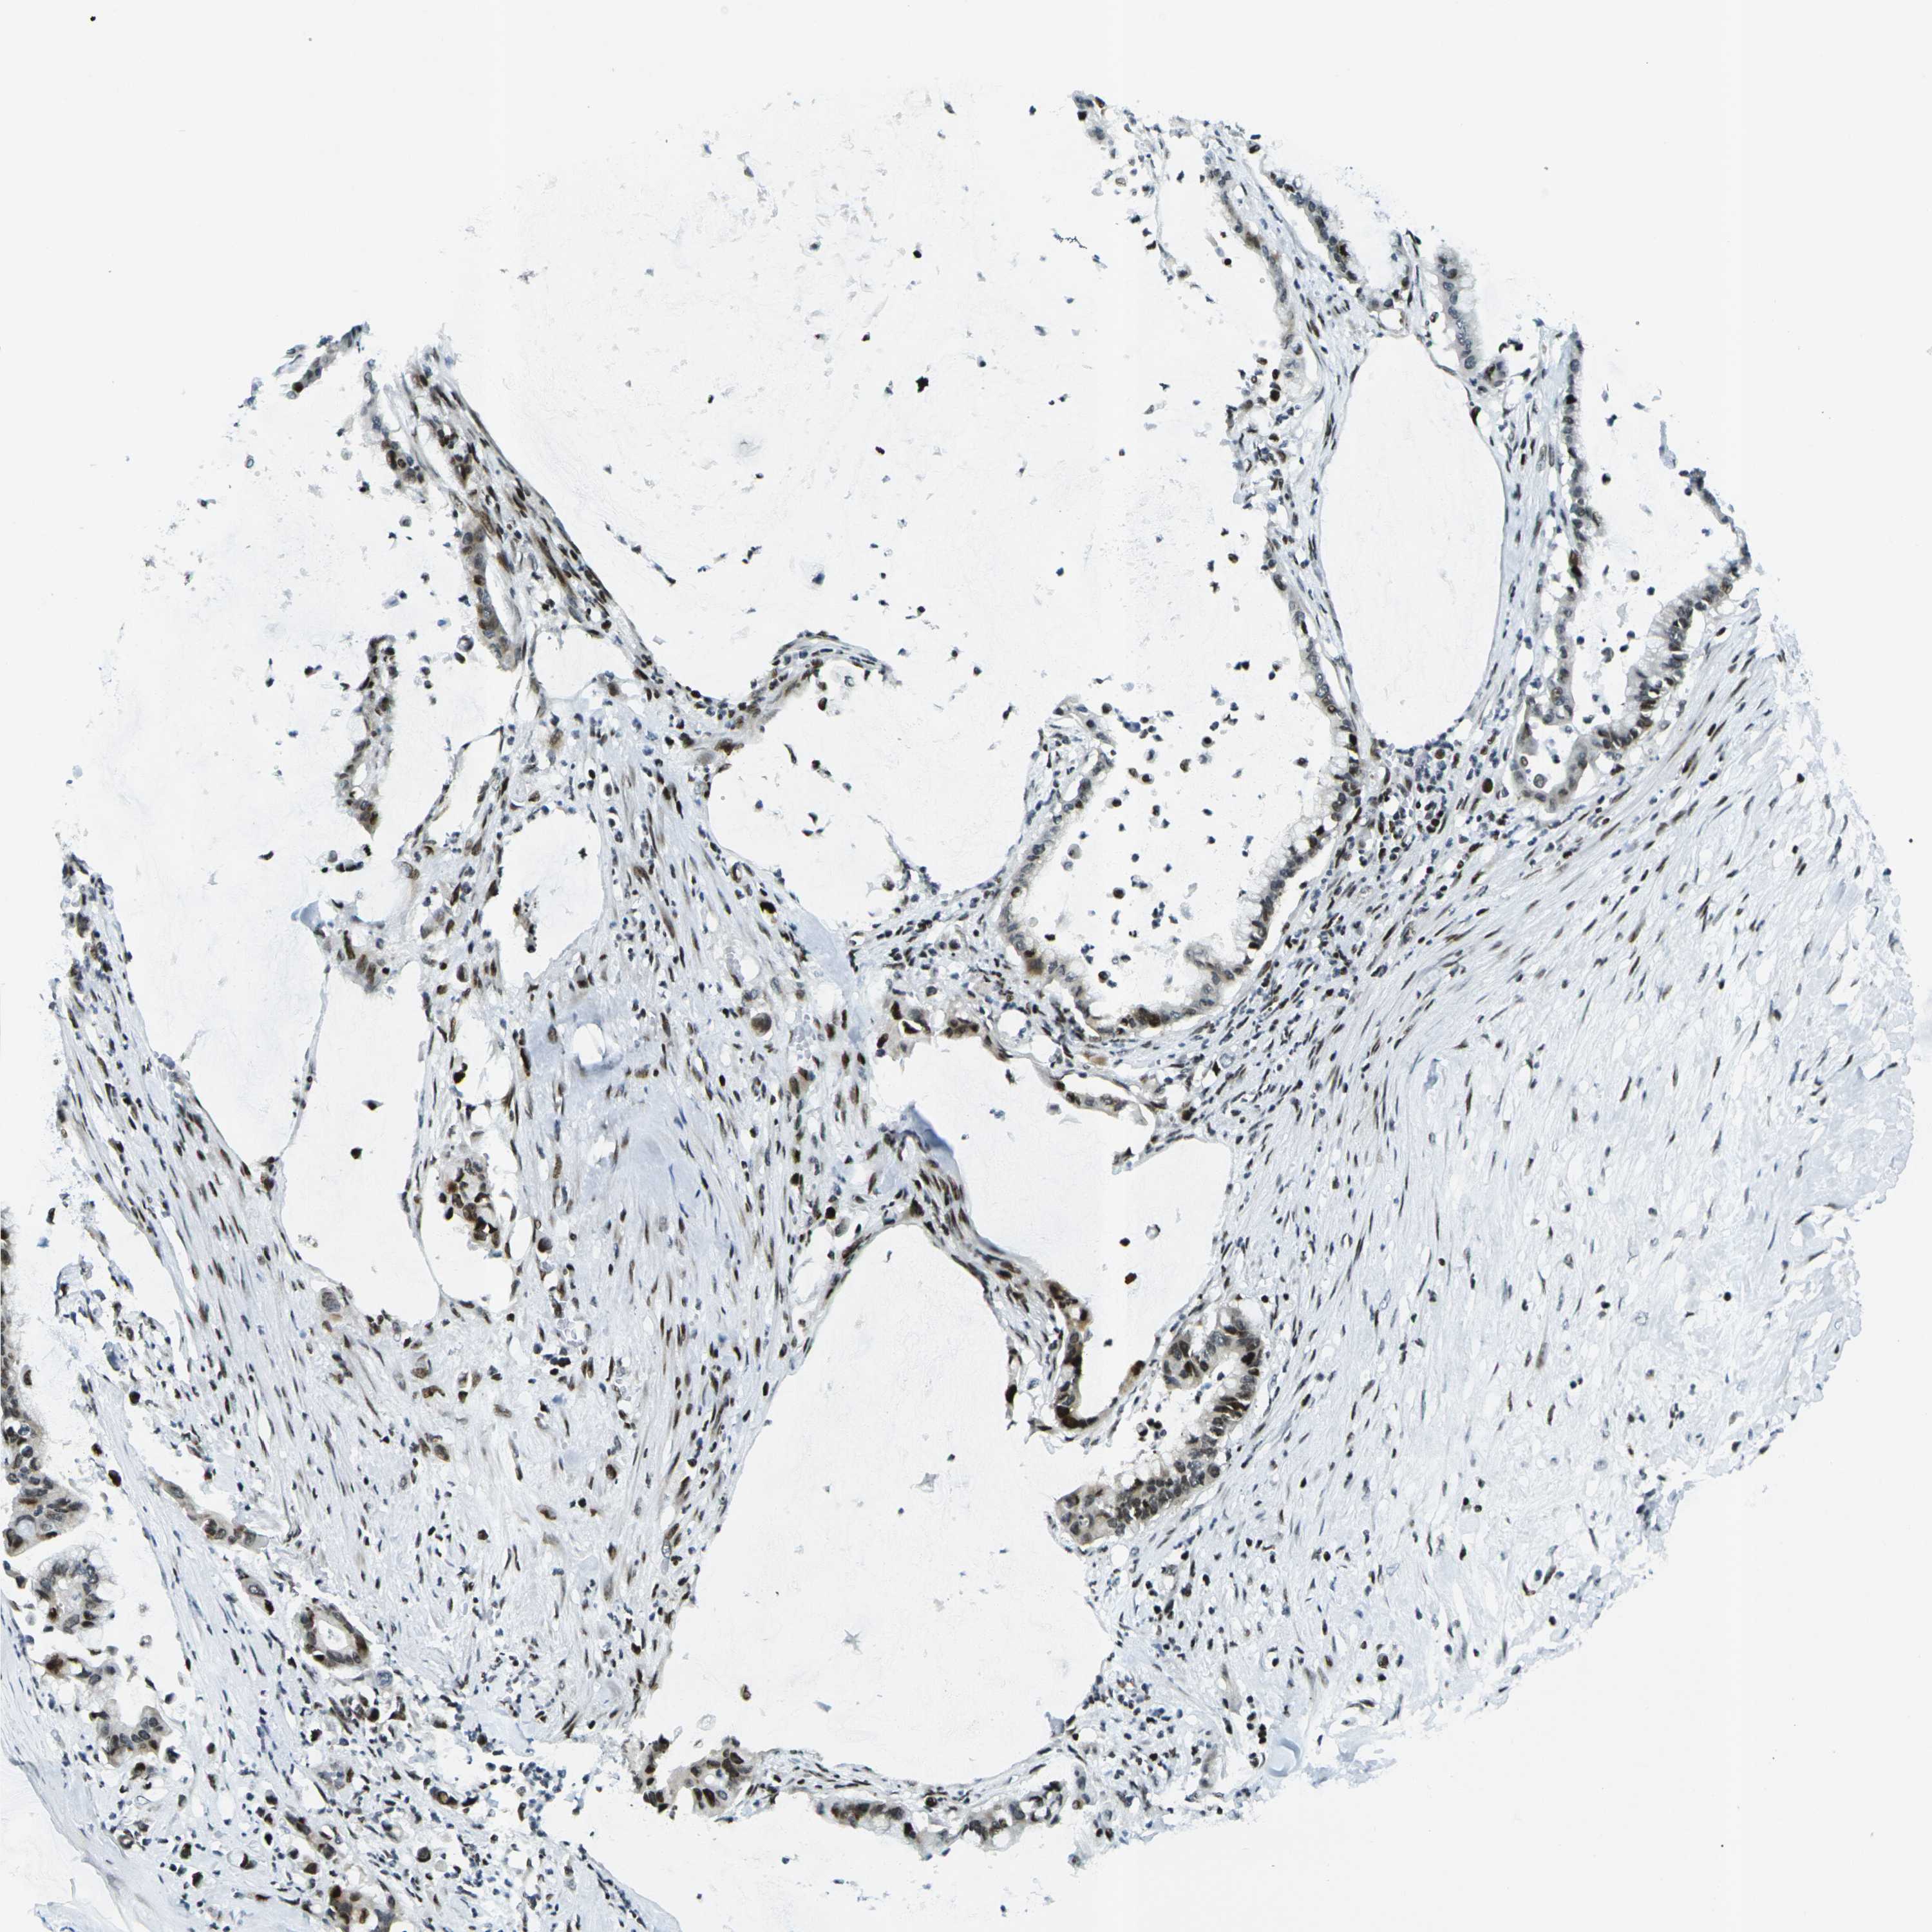

PANCREATIC CANCER - Protein expressioni

A mouse-over function shows sample information and annotation data. Click on an image to view it in a full screen mode. Samples can be filtered based on level of antibody staining by selecting one or several of the following categories: high, medium, low and not detected. The assay and annotation is described here.

Note that samples used for immunohistochemistry by the Human Protein Atlas do not correspond to samples in the TCGA dataset.

Antibody stainingi

Antibody staining in the annotated cell types in the current human tissue is reported as not detected, low, medium, or high, based on conventional immunohistochemistry profiling in selected tissues. This score is based on the combination of the staining intensity and fraction of stained cells.

Each image is clickable and will lead to virtual microscopy that enables deeper exploration of all samples and also displays staining intensity scores, fraction scores and subcellular localization as well as patient and tissue information for each sample.

Antibody CAB011481

Adenocarcinoma, metastatic, NOS